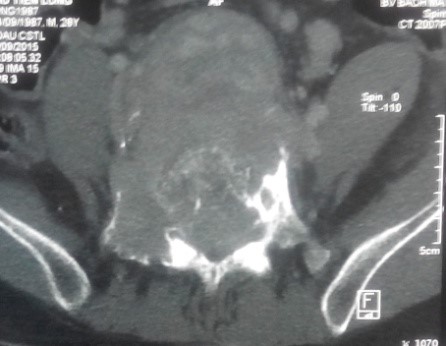

Trên X-quang, CT scanner khối u phá hủy vỏ xương gần hết thân và cuống sống L5.

CT scanner và MRI giúp đánh giá vỏ xương, tổn thương hủy xương cũng như mức độ thâm nhiễm quanh u. Trên T1W, T2W khối u TBKL đồng tín hiệu với tổ chức cơ, có thể giảm tín hiệu do collagen và hemosiderin, T1W sau tiêm ngấm thuốc. Phần mềm quanh u có thể hoại tử nhiễm trùng, đặc điểm này thường không gặp trong nang xương phình mạch, có thể để chẩn đoán phân biệt [5,11,12]. Bệnh nhân của chúng tôi, khối u phá vỡ thân đốt L5, thâm nhiễm phầm mềm rộng chèn ép ống sống phía sau, khối u cũng thâm nhiễm rộng ra phần mềm phía trước vào tiểu khung kích thước lớn khoảng 10 x 10cm, khối u đẩy lồi và một phần ôm lấy ngã ba chủ chậu ra phía trước gây khó khăn cho việc phẫu thuật lấy bỏ khối u và là yếu tố tiên lượng tái phát cao sau mổ.